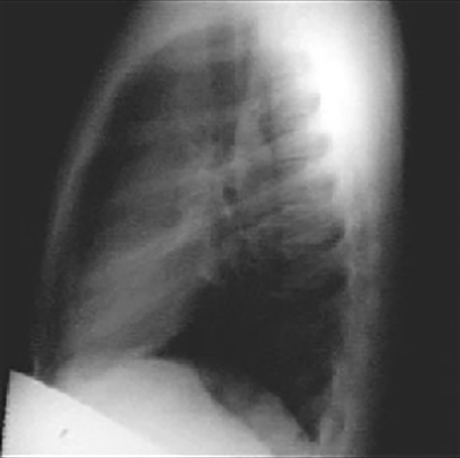

You are incorrect - the best interpretation of the chest X rays in our patient is that they are normal.

These chest X rays show a dilated ascending aorta.

The lateral view shows a dilated ascending aorta as evidenced by the shadow anterosuperior to the heart.